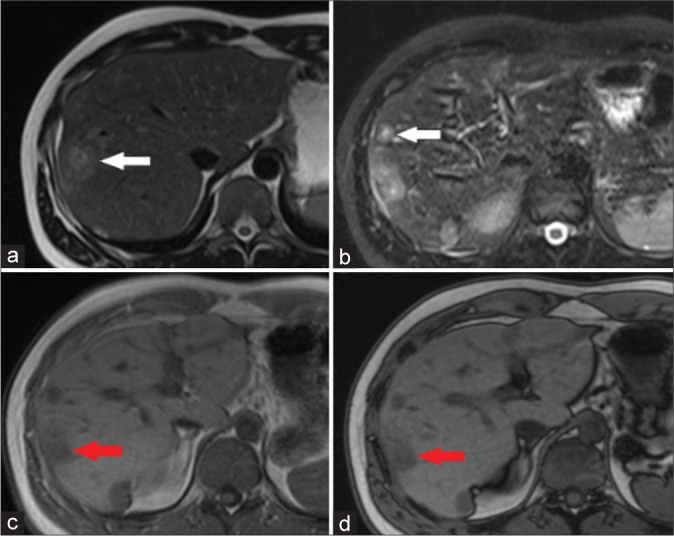

This study aims to provide a comprehensive understanding of primary hepatic angiosarcoma, a rare and aggressive malignancy, focusing on its diagnostic challenges and unique imaging characteristics. The objective is to delineate the distinctive features of angiosarcoma through computed tomography and magnetic resonance imaging modalities, contributing to improved diagnostic precision and adding valuable insights to the scientific literature. We present the case of a 25-year-old male with primary hepatic angiosarcoma, emphasizing the challenges in distinguishing it from other vascular tumors.